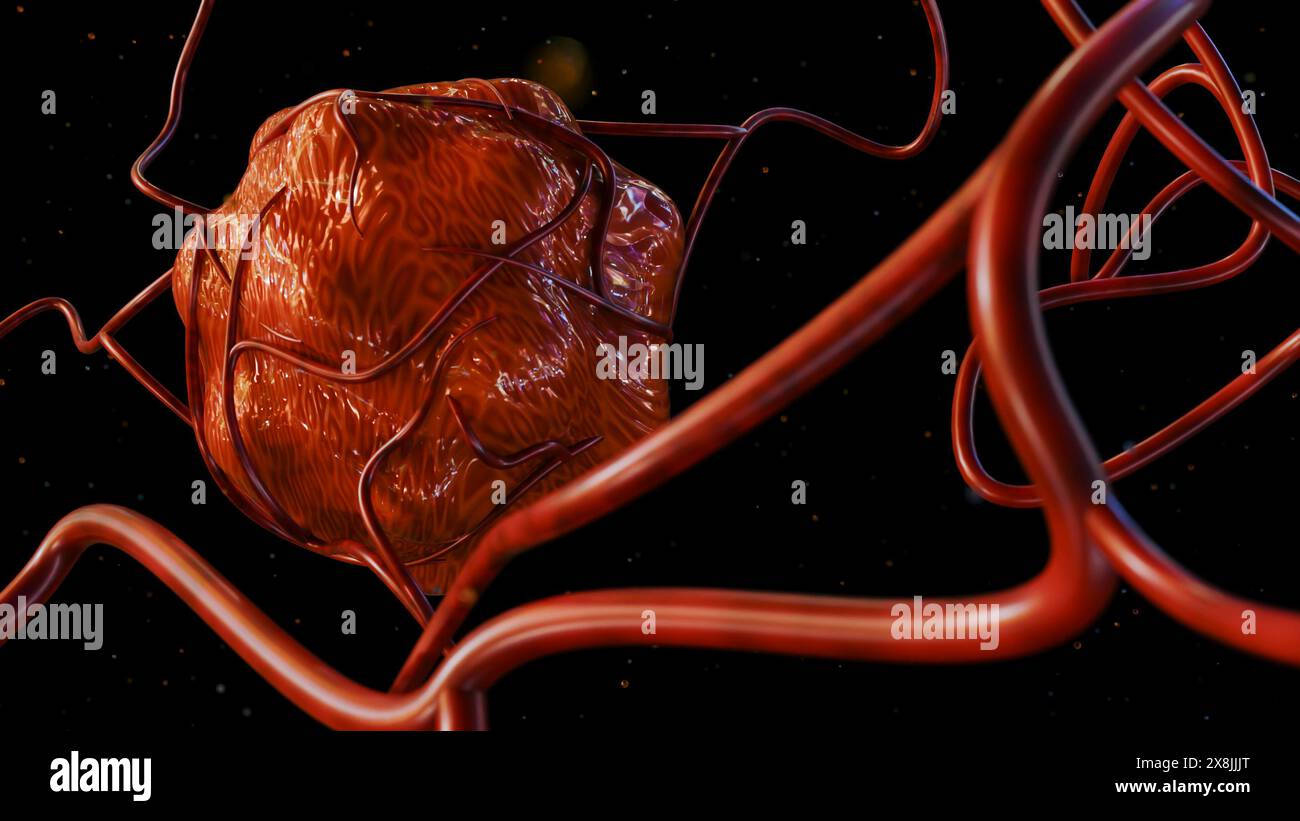

RF2X8JJJR–Die 3D-Darreichungsform von Krebs erfordert eine Blutversorgung, um die Nährstoffe und den Sauerstoff zu liefern, die sie zum Wachstum und Überleben benötigt

RF2X8JJJT–Die 3D-Darreichungsform von Krebs erfordert eine Blutversorgung, um die Nährstoffe und den Sauerstoff zu liefern, die sie zum Wachstum und Überleben benötigt

RF2X8JJJX–Die 3D-Darreichungsform von Krebs erfordert eine Blutversorgung, um die Nährstoffe und den Sauerstoff zu liefern, die sie zum Wachstum und Überleben benötigt